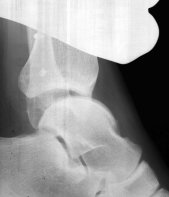

Das obere Sprunggelenk von vorne und von der Seite: alles sieht normal aus.

Dasselbe Gelenk in den «Gehaltenen Aufnahmen»: deutlich ist die vermehrte Aufklappbarkeit zu sehen, ein Zeichen dafür, dass seitlich der Halt der Bänder fehlt.